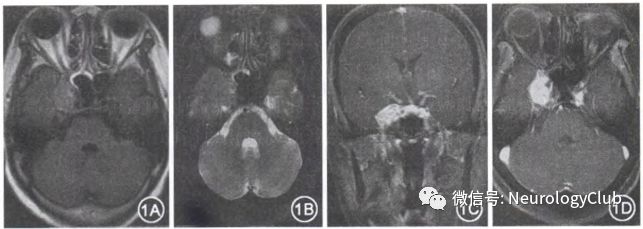

患者女,56岁,因上腭部肿物3年于2017年5月在济宁医学院附属医院口腔颌面外科行上颌骨肿物切除+上颌窦根治术,术后病理学诊断为(上颌骨)间叶源性肿瘤,而后又因头痛、右眼睑下垂10d于2017年7月入住济宁医学院神经内科。头痛主要为右侧半头部,呈阵发性,较为剧烈,无恶心、呕吐,无肢体抽搐,无意识不清。体格检查:右动眼神经麻痹症状,左侧下颌骨局部缺损,四肢肌力、肌张力正常,双侧巴氏征未引出,感觉检查无异常,双手指鼻稳准。入院颅脑MRI平扫加增强示:右侧鞍旁占位性病变,考虑脑膜瘤可能性大,不典型硬脑膜海绵状血管瘤待排(图1);全脑血管造影未见明显血管异常。

(图1:颅脑MRI平扫,右侧鞍旁可见一团块状T1WI[1A]T2WI[1B]信号灶,大小约2.4cm×2.2cm×1.4cm,边缘清楚,增强扫描后呈明显均匀性强化,可见“脑膜尾征”[1C-D]